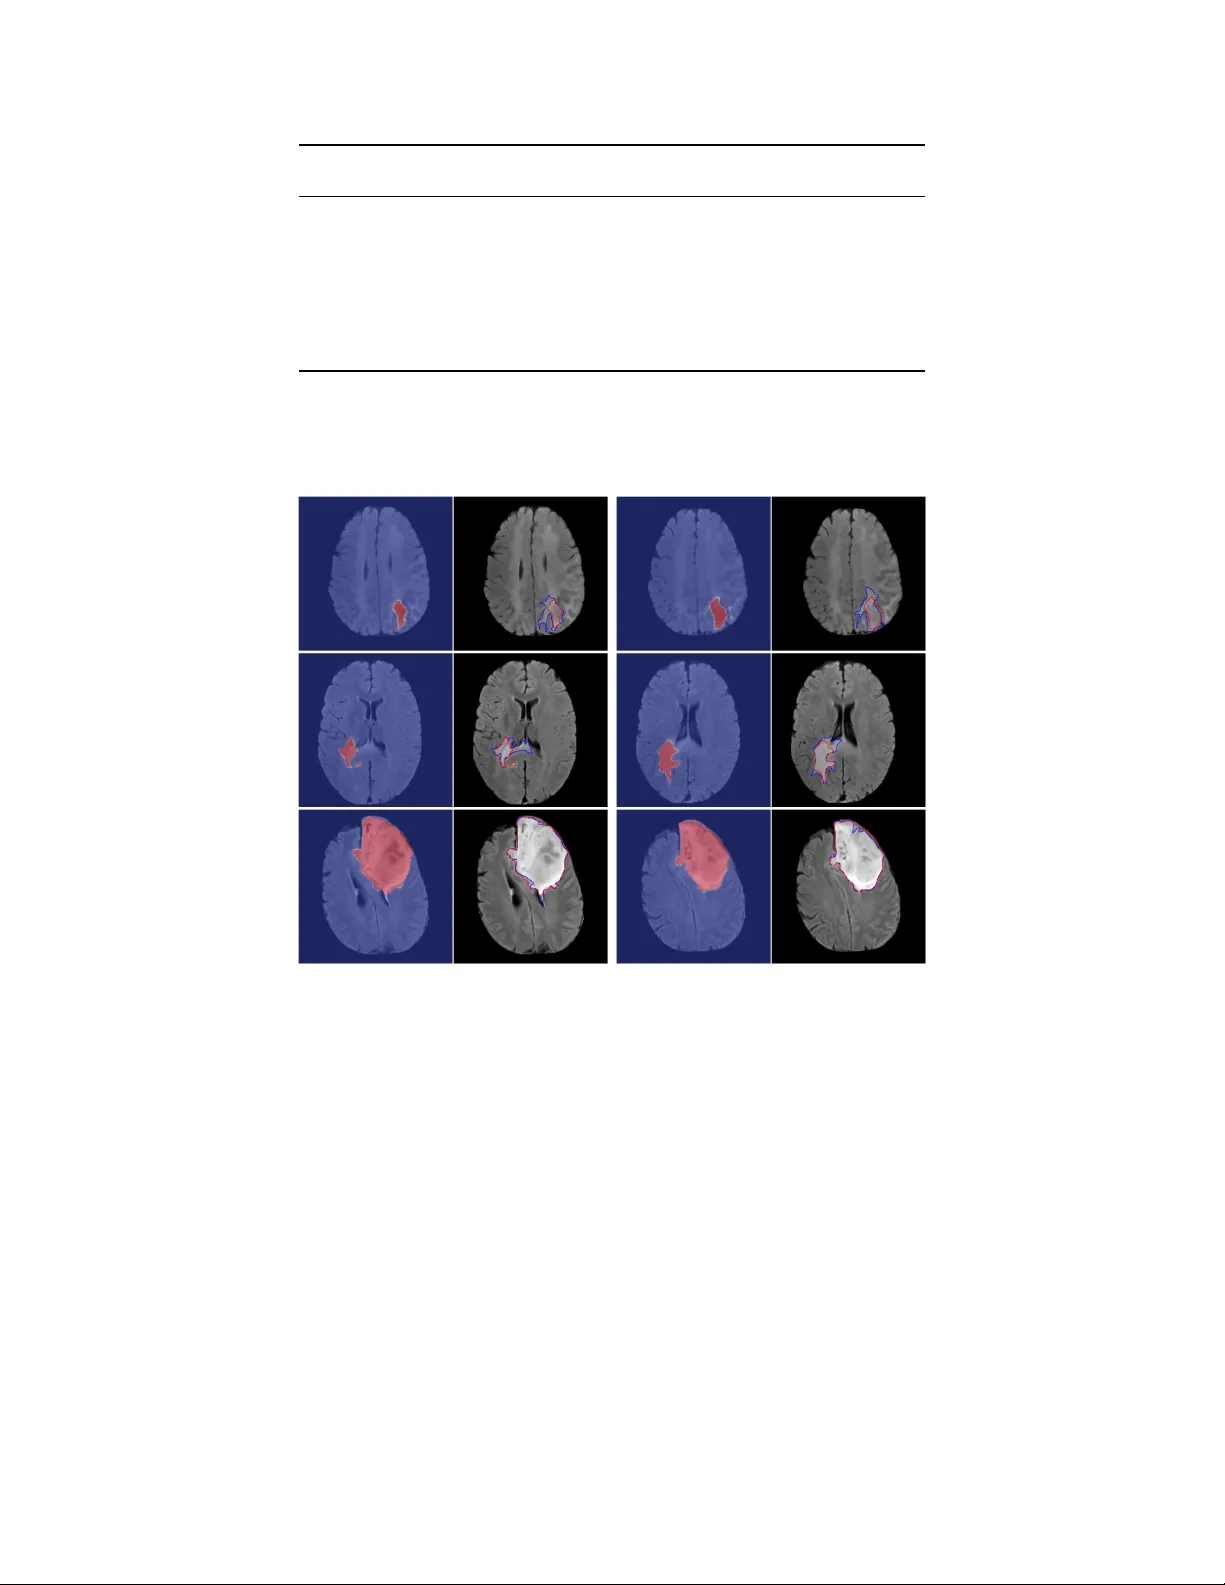

Asso ciation of genomic subt yp es of lo w er-grade gliomas with shap e features automatically extracted b y a deep learning algorithm Mateusz Buda 1 , Ashirbani Saha 1 , Maciej A. Mazuro wski 1, 2 1 Departmen t of Radiology , Duke Universit y , Durham, NC 2 Departmen t of Electrical and Computer Engineering, Duk e Univ ersity , Durham, NC Abstract Recen t analysis identified distinct genomic subt yp es of low er-grade glioma tumors which are asso ciated with shap e features. In this study , w e propose a fully automatic w ay to quantify tumor imaging c haracteristics using deep learning-based segmentation and test whether these c haracteristics are predictiv e of tumor genomic subt yp es. W e used preop erative imaging and genomic data of 110 patien ts from 5 institutions with lo wer-grade gliomas from The Cancer Genome Atlas. Based on automatic deep learning seg- men tations, we extracted three features which quan tify tw o-dimensional and three-dimensional c haracteristics of the tumors. Genomic data for the analyzed cohort of patien ts consisted of previously iden tified genomic clusters based on IDH mutation and 1p/19q co-deletion, DNA meth ylation, gene expression, DNA copy num b er, and microRNA expression. T o analyze the relationship betw een the imaging features and genomic clusters, we conducted the Fisher exact test for 10 h ypotheses for each pair of imaging feature and genomic subt ype. T o account for m ultiple h yp othesis testing, we applied a Bonferroni correction. P-v alues lo wer than 0.005 were considered statistically significant. W e found the strongest association b etw een RNASeq clusters and the b ounding ellipsoid v olume ratio ( p < 0 . 0002) and b et ween RNASeq clusters and margin fluctuation ( p < 0 . 005). In addition, we identified asso ciations b et ween b ounding ellipsoid v olume ratio and all tested molecular subtypes ( p < 0 . 02) as well as betw een angular standard deviation and RNASeq cluster ( p < 0 . 02). In terms of automatic tumor segmen tation that was used to ge nerate the quan titative image characteristics, our deep learning algorithm achiev ed a mean Dice co efficien t of 82% which is comparable to human performance. Keyw ords: deep learning; brain segmen tation; radiogenomics; MRI; LGG 1 1 In tro duction Lo wer-grade gliomas (LGG) are a group of WHO grade I I and grade II I brain tumors. As opp osed to grade I which are often curable by surgical resection, grade I I and I I I are infiltrativ e and tend to recur and evolv e to higher-grade lesion. Predicting patient outcomes based on histopathologi- cal data for these tumors is inaccurate and suffers from in ter-observ er v ariability [ 1 ]. One of the promising metho ds that might address this issue is defining subtypes of LGG through clustering of patien ts based on DNA methylation, gene expression, DNA copy n umber, and microRNA expres- sion [ 1 ]. It was shown that the clusters iden tified in suc h wa y are to a large extent in agreemen t with another basic molecular subtype based on IDH (IDH1 and IDH2) m utation and 1p/19q co- deletion [ 1 , 2 ]. P atients with tumors from different molecular groups substan tially differ in terms of t ypical course of the disease and ov erall surviv al [ 3 ]. A new research direction in cancer, called radiogenomics, aims at inv estigating the relationship b et w een tumor genomic c haracteristics and medical imaging [ 4 ]. Imaging can pro vide important information before surgery or in cases when resection is not p ossible. V ery recen t studies in this area hav e disco vered an asso ciation of tumor shap e features extracted from MRI with its genomic subt yp es [ 5 , 6 ]. How ev er, the first step when extracting tumor features w as the manual segmen tation of MRI. Such annotation is costly , time consuming and results in annotations with high inter-rater v ariance [ 7 ]. Deep learning is a new field of machine learning that is recen tly rev olutionizing the automated analysis of images [ 8 , 9 ]. There are man y examples of successful applications of deep learning in medical imaging [ 10 , 11 , 12 , 13 , 14 ] and more sp ecifically in brain MRI segmentation [ 15 ]. In recent y ears, progress in deep learning for automatic brain segmentation matured to a level that ac hiev es p erformance of a skilled radiologist [ 16 ]. Most of these efforts are focused on glioblastoma rather than LGG. Dev elopment of mo dels that yield high qualit y segmentation of LGG in brain MRI w ould p otentially allow for automatization of the pro cess of tumor genomic subtype identification through imaging that is fast, inexp ensiv e, and free of in ter-reader v ariabilit y . In this study , w e combine the field of deep learning and radiogenomic and prop ose a fully automatic algorithm for quan tification of tumor shap e and test whether the assessed shape features are prognostic of tumor molecular subt yp es. Developing imaging-biomark ers that could inform of tumor genomics w ould pro vide the information to clinicians sooner in a non-inv asiv e w ay and in some cases could allo w for b etter stratification of tumors where resection is not p erformed. In this 2 study , w e show promise for ev entually developing such imaging-based biomark ers. The reminder of this pap er is organized as follows. Section 2 describ es data used in our study whereas section 3 describes segmen tation mo del, features used for tumor quan tification, and sta- tistical metho ds. Then, in section 4 we show results for the segmentation algorithm and prediction of genomic subt yp es. In section 5 w e discuss our findings. Finally , sections 6 and 7 are dev oted to limitations and conclusions of the study , resp ectiv ely . 2 Dataset 2.1 P atien t p opulation The data used in this study w as obtained from The Cancer Genome A tlas (TCGA) and The Cancer Imaging Archiv e (TCIA). W e identified 120 patien ts from TCGA lo wer-grade glioma collection 1 who had preop erativ e imaging data av ailable, con taining at least a fluid-atten uated inv ersion recov ery (FLAIR) sequence. T en patients had to b e excluded since they did not ha ve genomic cluster information av ailable. The final group of 110 patients w as from the follo wing 5 institutions: Thomas Jefferson Univ ersity (TCGA-CS, 16 patients), Henry F ord Hospital (TCGA-DU, 45 patien ts), UNC (TCGA-EZ, 1 patient), Case W estern (TCGA-FG, 14 patients), Case W estern – St. Joseph’s (TCGA-HT, 34 patien ts) from TCGA LGG collection. The complete list of patients used in this study is included in Online Resource 1. The en tire set of 110 patients was split into 22 non- o verlapping subsets of 5 patients eac h. This was done for ev aluation with cross-v alidation. 2.2 Imaging data Imaging data was obtained from The Cancer Imaging Arc hive 2 whic h con tains the images corre- sp onding to the TCGA patien ts and is sp onsored by the National Cancer Institute. W e used all mo dalities when a v ailable and only FLAIR in case any other modality w as missing. There were 101 patien ts with all sequences av ailable, 9 patients with missing p ost-con trast sequence, and 6 with missing pre-con trast sequence. The complete list of av ailable sequences for each patient is included in Online Resource 1. The n umber of slices v aried among patien ts from 20 to 88. In order to capture the original pattern of tumor growth, we only analyzed preop erativ e data. The assessment of tumor shap e was based on FLAIR abnormalit y since enhancing tumor in LGG is rare. 1 https://cancergenome.nih.gov/cancersselected/lowergradeglioma 2 https://wiki.cancerimagingarchive.net/display/Public/TCGA- LGG 3 A researc her in our lab oratory , who w as a medical school graduate with experience in neuroradi- ology imaging, manually annotated FLAIR images by dra wing an outline of the FLAIR abnormalit y on eac h slice to form training data for the automatic segmen tation algorithm. W e used soft ware dev elop ed in our lab oratory for this purp ose. A board eligible radiologist v erified all annotations and mo dified those that w ere identified as incorrect. Dataset of registered images together with man ual segmentation masks for each case used in our study is released and made publicly av ailable at the follo wing link: https://kaggle.com/mateuszbuda/lgg- mri- segmentation . 2.3 Genomic data Genomic data used in this study consisted of DNA meth ylation, gene expression, DNA copy n umber, and microRNA expression, as w ell as IDH m utation 1p/19q co-deletion measurement. Sp ecifically , in our analysis we consider six previously identified molecular classifications of LGG that are kno wn to b e correlated with some tumor shap e features [ 6 ]: 1. Molecular subtype based on IDH mutation and 1p/19q co-deletion (three subtypes: IDH m utation-1p/19q co-deletion, IDH mutation-no 1p/19q co-deletion, IDH wild type) 2. RNASeq clusters (4 clusters: R1-R4) 3. DNA meth ylation clusters (5 clusters: M1-M5) 4. DNA cop y num b er clusters (3 clusters: C1-C3) 5. microRNA expression clusters (4 clusters: mi1-mi4) 6. Cluster of clusters (3 clusters: co c1-coc3) 3 Metho ds 3.1 Automatic segmen tation Figure 1 shows the o verview of the segmen tation algorithm. The follo wing phases comprise the fully automatic algorithm for obtaining the segmen tation mask: image preprocessing, segmentation, and p ost-processing. Then, once the segmen tation masks are generated, w e extracted shap e features that were iden tified as predictive of molecular subt yp es. The following sections provide details on eac h of the steps. Source co de of the algorithm described in this section is also av ailable at the follo wing link: https://github.com/mateuszbuda/brain- segmentation . 4 Figure 1: A sc hema sho wing data processing steps of our system for molecular subtype inference from a sequence of brain MRI 3.1.1 Prepro cessing Images v aried significan tly b et ween patien ts in terms of size. The prepro cessing of the image sequences consisted of the follo wing steps: • Scaling of the images to the common frame of reference. • Remo v al of the skull to fo cus the analysis on the brain region (a.k.a., skull stripping). • Adaptiv e window and lev el adjustment based on the image histogram to normalize intensities of tissues b et w een cases. • Z-score normalization of the en tire data set. The details of all the pre-pro cessing steps are included in the Online Resource 2. 3.1.2 Segmen tation The main segmentation step was performed using a fully conv olutional neural net work with the U-Net architecture [ 10 ] sho wn in Figure 2. It comprises four lev els of blo c ks con taining tw o con- v olutional la yers with ReLU activ ation function and one max p ooling lay er in the encoding part and up-conv olutional la yers instead in the deco ding part [ 17 , 18 , 19 , 20 , 21 ]. Consistent with the U-Net arc hitecture, from the enco ding lay ers we use skip connections to the corresp onding lay ers in the deco ding part. They pro vide a shortcut for gradient flo w in shallo w lay ers during the training phase [ 22 ]. Man ual segmen tation serv ed as a grou nd truth for training a mo del for automatic segmentation. W e trained tw o netw orks, one for cases with three sequences av ailable (pre-con trast, FLAIR, and p ost-con trast) and the other that used only FLAIR. F or the second net w ork, instead of missing sequences w e used neigh b oring FLAIR slices from b oth sides of a slice of in terest as additional c hannels. Since in this scenario the tw o sequences, whic h o ccupied channel 1 and channel 3 of the input are not av ailable, we filled these channels with neighboring tumor slices to pro vide additional information to the net work. 5 Input 256x256x3 Conv 3x3, ReLU 256x256x32 Max pooling 2x2 128x128x32 Concatenation Conv 3x3, ReLU 128x128x64 Max pooling 2x2 64x64x64 Conv 3x3, ReLU 64x64x128 Max pooling 2x2 32x32x128 Conv 3x3, ReLU 32x32x256 Max pooling 2x2 16x16x256 Conv 3x3, ReLU 16x16x512 Conv 3x3, ReLU 16x16x512 Up-conv 2x2 32x32x256 Conv 3x3, ReLU 32x32x256 Up-conv 2x2 64x64x128 Conv 3x3, ReLU 64x64x128 Up-conv 2x2 128x128x64 Conv 3x3, ReLU 128x128x64 Up-conv 2x2 256x 256x32 Conv 3x3, ReLU 256x256x32 Conv 1x1, Sigmoid 256x256x1 Conv 3x3, ReLU 256x256x32 Conv 3x3, ReLU 128x128x64 Conv 3x3, ReLU 64x64x128 Conv 3x3, ReLU 32x32x256 Conv 3x3, ReLU 32x32x256 Conv 3x3, ReLU 64x64x128 Conv 3x3, ReLU 128x128x64 Conv 3x3, ReLU 256x256x32 Figure 2: U-Net architecture used for skull stripping and segmentation. Below eac h la yer sp ecification w e pro vide dimensionality of a single example that this la yer outputs The n umber of slices containing tumor w as considerably low er than those with only background class present. Therefore, to accoun t for this fact, we applied ov ersampling with data augmen tation that was pro ved to help in training conv olutional neural netw orks [ 23 ]. W e did it by ha ving three instances of eac h tumor slice in our training set. F or one o versampled slice w e applied random rotation b y 5 to 15 degrees and for the other slice w e applied random scale b y 4% to 8%. T o further reduce the imbalance b etw een tumor and non-tumor pixels, w e discarded empty slices that did not con tain an y brain or other tissue after applying skull stripping. This step has b een undertak en since training a fully conv olutional neural netw ork with image s that do not contain an y p ositiv e v oxels can be highly detrimental. Please note that a significant ma jority of vo xels in the abnormal slices are still normal and therefore sufficien t negative data is a v ailable for training. 6 3.1.3 P ost-pro cessing T o further impro v e the accuracy , w e implemented a post-pro cessing algorithm that remov es false p ositiv es. Specifically , w e extracted all tumor volumes using connected comp onen ts algorithm on a three-dimensional segmentation mask for each patien t. W e did it using 6-connected pixels in three dimensions, i.e. neigh b oring pixels are defined as b eing connected along primary axes. Ev entually , w e included in the final segmentation mask only the pixels comprising the largest connected tu- mor volume. This p ost-pro cessing strategy b enefits extraction of shap e features (describ ed in the follo wing section) since they are sensitive to isolated false p ositive pixel segmentations. 3.1.4 Extraction of shap e features W e consider three shape features of a segmen ted tumor that w ere identified as imp ortan t in the con text of low er grade glioma radiogenomic [ 6 ]: A ngular standar d deviation (ASD) is the av erage of the radial distance standard deviations from the centroid of the mass across ten equiangular bins in one slice, as describ ed in [ 24 ]. Before calculating the v alue of this feature, w e normalize radial distances to ha ve mean equal one. Angular standard deviation of a tumor shap e is a quan titative measure of v ariation in the tumor margin within relatively small parts of the tumor. It also captures non-circularit y of the tumor, i.e. lo w v alue indicates circle like shap e. Bounding el lipsoid volume r atio (BEVR) is the ratio b et ween the v olume of segmented FLAIR abnormalit y and its minim um b ounding ellipsoid. This feature captures the irregularit y of the tumor in three dimensions. If the tumor fits well into its b ounding ellipsoid (high v alue of BEVR), it is considered more regular while if more space in the b ounding ellipsoid is unfilled, the shap e is considered irregular. Mar gin fluctuation (MF) is computed as follows. First, we find the centroid of the tumor and distances from it to all pixels on the tumor boundary in one slice. Then, we apply a veraging filter of length equal to 10% of the tumor p erimeter measured in the num b er of pixels. Margin fluctuation is the standard deviation of the difference b et ween v alues b efore and after smo othing, i.e. applying a veraging filter. Similarly as in ASD, radial distances are normalized to hav e a mean of one. This is done in order to remov e the impact of tumor size on the v alue of this feature. Margin fluctuation is a tw o-dimensional feature that quan tifies the amoun t of high frequency c hanges, i.e. smoothness of the tumor b oundary and w as previously used for analysis of spiculation in breast tumors [ 25 , 26 ]. 7 3.2 Statistical analysis Our hypothesis was that fully automatically-assessed shap e features are predictive of tumor molec- ular subt yp es. Since we considered 6 definitions of molecular subt yp es based on genomic assa ys and multiple imaging features, we fo cused our analysis on the relationships betw een imaging and genomics that w ere found significan t (with man ual tumor segmen tation) in a previous study [ 6 ]. Sp ecifically , those were the follo wing relationships: b ounding ellipsoid v olume ratio with RNASeq, miRNA, CNC, and COC, the relationship of Margin fluctuation with RNASeq, and the relationship of angular standard deviation with IDH/1p19q, RNASeq, Methylation, CNC, and COC resulting in 10 sp ecific hypotheses. T o assess statistical significance of these asso ciations, we conducted the Fisher exact test (fisher.test function in R) for each of 10 com binations of imaging and genomics. F or the purp ose of this test, we turned eac h contin uous imaging v ariable v alue into a num b er from 1 to 4 based on which quartile of the feature v alue it fell into. F or each of the imaging and genomic feature com binations, we used only the cases that had b oth: imaging and genomic subtype data a v ailable. W e conducted a total of 10 statistical tests for eac h pair of imaging feature and genomic subt yp e for our primary hypothesis. T o accoun t for m ultiple h yp othesis testing, w e applied a Bonferroni correction. P-v alues lo w er than 0.005 (0.05/10) w ere considered statistically significant for our primary radiogenomics h yp otheses. Additionally , w e ev aluated performance of the deep learning-based segmentation itself. W e used Dice similarit y coefficient [ 27 ] as the ev aluation metric which measures the ov erlap b et ween the segmen tation provided by the algorithm and the man ually-annotated gold standard. In the ev aluation pro cess, we used cross-v alidation. Sp ecifically , we divided our en tire dataset in to 22 subsets, each con taining exactly 5 cases. The mo del training was conducted on the training subsets and then the model w as applied to the test cases. This was rep eated 22 times un til eac h subset s erv ed once as the test set. The cases then w ere p ooled for the analysis as describ ed ab o ve. The n umber of cases included in the training and test sets (whic h determines the num b er of folds) is a trade-off b et ween computational cost of training m ultiple mo dels and having more data to train eac h of them. The t wo extremes of this approach are lea ve-one-out strategy which results in one-case folds and the other is 50% split whic h giv es 2 folds. W e found folds of 5 patien ts to b e a go od balance b et ween a training set size and computational cost. 8 4 Results The patients’ c haracteristics are sho wn in T able 1. The a verage patien t age w as 47. Fift y six of the patients were w omen, fifty three w ere men, and the gender of one was unknown. The tumors’ c haracteristics are provided in T able 2. There w ere three histological types of tumors: oligo dendroglioma (47), astro cytoma (33), oligoastro cytoma (29), and one unknown. Grade of the tumors in our data included 51 cases of grade I I, 58 of grade I I I, and grade of one tumor was unkno wn. Characteristic P atients (N=110) Age (y ears) Median 47 Range 20-75 Gender F emale 56 Male 32 Not a v ailable 1 T able 1: Patien t characteristic. Age for one patient w as missing and was ignored in the calculation. The results of the radiogenomic analysis are shown in Figure 3. W e confirmed our primary h y- p othesis for t wo pairs of imaging features and genomic subt yp e. W e found the strongest asso ciation b et w een RNASeq cluster and the b ounding ellipsoid volume ratio ( p < 0 . 0002) along with margin fluctuation ( p < 0 . 005). In addition, we iden tified considerable correlations for the b ounding el- lipsoid volume ratio and all tested molecular subtypes ( p < 0 . 02) as well as for angular standard deviation and RNASeq cluster ( p < 0 . 02). In T able 3 w e provide R OC AUC scores for the task of discriminating eac h RNASeq cluster from all other subtypes based on shap e features extracted from segmentation masks obtained with the deep learning algorithm and compare them to man ual segmentations. W e selected RNASeq cluster since it sho wed the strongest association with shap e features. In addition, w e included ROC A UC based on tw o demographic v ariables, i.e. age and gender. The results sho w that deep learning w as able to pro vide tumor segmen tations of a quality that allow ed for extraction of shap e features that match man ual segmen tations. Sp ecifically , cluster R2 was distinguished from all other clusters 9 based on in versed bounding ellipsoid v olume ratio with AUC of 0.80 and 0.78 for deep learning- based and manual segmentations, respectively . In terms of angular standard deviation, A UC for deep learning w as 0.73 and for man ual segmen tations w as 0.72. The predictive v alue of demographic v ariables for R2 cluster was notably lo wer with AUC=0.66 for age and A UC=0.50 for gender. A detailed comparison of man ual and automatic segmentation for the task of discriminating cluster R2 from all other clusters with resp ect to sensitivity , sp ecificit y , p ositiv e predictiv e v alue, and negativ e predictive v alue is given in Online Resource 1. In terms of tumor segmen tation, our deep learning algorithm ac hiev ed mean Dice co efficient of 82% and median Dice co efficien t of 85%. F or the 101 cases with all sequences av ailable, mean and median Dice co efficien t was the same as for all 110 cases. F or the remaining 9 cases segmen ted based on FLAIR sequence only , mean and median Dice co efficien t was 82% and 88%, resp ectively . Characteristic Cases (N=110) Histologic t yp e and grade Astro cytoma Grade I I 8 Grade I II 25 Oligoastro cytoma Grade I I 14 Grade I II 21 Oligo dendroglioma Grade I I 29 Grade I II 18 Not a v ailable 1 IDH-1p/19q subt yp e IDH m utation, 1p/19q co-deletion 26 IDH m utation, no 1p/19q co-deletion 56 IDH wild t yp e 25 Not a v ailable 3 T able 2: T umor characteristic. 10 R1 R2 R3 R4 RNASeq cluster 0.2 0.25 0.3 0.35 0.4 0.45 0.5 0.55 Bounding ellipsoid volume ratio mi1 mi2 mi3 mi4 miRNA cluster 0.2 0.25 0.3 0.35 0.4 0.45 0.5 0.55 Bounding ellipsoid volume ratio C1 C2 C3 CNC cluster 0.2 0.25 0.3 0.35 0.4 0.45 0.5 0.55 Bounding ellipsoid volume ratio coc1 coc2 coc3 COC cluster 0.2 0.25 0.3 0.35 0.4 0.45 0.5 0.55 Bounding ellipsoid volume ratio R1 R2 R3 R4 RNASeq cluster 0.02 0.04 0.06 0.08 0.1 Margin fluctuation IDHmut-codel IDHmut-nocodel IDHwt Molecular subtype (IDH, 1p/19q) 0.05 0.1 0.15 0.2 0.25 Angular standard deviation R1 R2 R3 R4 RNASeq cluster 0.05 0.1 0.15 0.2 0.25 Angular standard deviation M1 M2 M3 M4 M5 Methylation cluster 0.05 0.1 0.15 0.2 0.25 Angular standard deviation C1 C2 C3 CNC cluster 0.05 0.1 0.15 0.2 0.25 Angular standard deviation coc1 coc2 coc3 COC cluster 0.05 0.1 0.15 0.2 0.25 Angular standard deviation Figure 3: Box and whisker plots demonstrating the relationship betw een tested genomic clusters and imaging features that quantify tumor shape Examples of segmen tations that we obtained alongside with ground truth masks for cases of v ary- ing performance of our segmen tation algorithm are presented in Figure 4. Due to max po oling la yers included in the U-Net arc hitecture which allo w for pro cessing of large volumes on currently a v ailable computers, the automated segmentation is less sensitive to high curv ature and sulcation and therefore, the pro duced masks tend to b e more smo oth comparing to manual segmentations. 11 V ariable R1 R2 R3 R4 Deep learning ASD 0.26 0.73 0.53 0.47 Deep learning 1/BEVR 0.23 0.80 0.36 0.53 Age 0.29 0.66 0.72 0.41 Gender 0.44 0.50 0.58 0.52 T able 3: R OC A UCs of shap e features and demographic v ariables for the task of discriminating one RNASeq cluster from all others. Figure 4: Examples of automatic segmentation for low (top), mo derate (middle), and high (b ottom) agree- men t with ground truth. Their Dice coefficient is 50%, 82% and 95% resp ectiv ely . In each pair, the first image sho ws a heatmap of ra w mo del output and in the second image blue outline corresp onds to ground truth and red to postpro cessed automatic segmentation output. Images show FLAIR mo dalit y after prepro cessing and skull stripping. Giv en small sample size, we additionally assessed the stabilit y and p erformance of our segmen- tation model using predictions generated for noisy input. F or eac h input image, w e applied additiv e Gaussian noise with zero mean and standard deviation equal to 10% and 20% of standard devia- tion computed on the training data. In the first case with 10% noise level, mean Dice co efficien t decreased to 81%. After increasing noise level to 20%, mean Dice co efficien t further decreased to 79%. In b oth cases, median Dice co efficien t was 85%. 12 5 Discussion In this study , w e were able to demonstrate that fully automatically-assessed imaging features of lo w grade gliomas are asso ciated with tumor molecular subtypes established using genomic analysis. The strength of these asso ciations w as sho wn to b e mo derate. Deep learning algorithms were used to segmen t the tumors. Using imaging to predict tumor genomics is of very high imp ortance and if accurate mo dels are developed, it could b e incorporated in the curren t treatment paradigm in a v ariet y of w ays. In the simplest scenario, if the mo del is highly accurate, it could simply replace the genomic analysis altogether. Curren t state of the art radiogenomic models, suc h as the one shown in this pap er whic h represen ts mo derate predictive p erformance, do not yet justify such substitution. Ho wev er, there are other w ays in whic h ev en mo dels with mo derate p erformance could contribute v aluable information. The imaging data is av ailable early in the pro cess and therefore approximate assessmen t of tumor biology b efore the surgery could still b e of help in guiding the next steps. The appro ximate imaging surrogate of molecular subt yp e w ould also be of particular use for patien ts that do not immediately undergo surgical excision of the tumor. In such case, in the absence of tissue analysis, the appro ximate classification by imaging could b e of very high v alue since genomic subt yp es are highly correlated with patient outcomes. If biopsy results are av ailable for a tumor that has not b een fully resected, the imaging surrogate of subtype can still b e of use given a p otential high intra-tumor heterogeneit y of the lesions and therefore a p ossibility that a local biopsy do es not accurately reflect the ov erall genomics of a tumor. Imaging offers a complete view of a tumor. Finally , even if the ov erall accuracy is not p erfect, it migh t b e p ossible to op erate at a high p ositiv e predictiv e v alue or high predictiv e v alue and the surrogate imaging-based mo dels of genomic subtypes could b e still used for triaging patients for genomic tests, ev en if it is a small minorit y of the patients. F or example, if based on imaging there is a high confidence that a tumor is of a particular aggressiv e subt yp e, the patien t could b e treated accordingly without additional exp ensiv e and in v asive genomic testing. If on the other hand the imaging-based mark er has lo w confidence, then additional genomic test could b e ordered. An imp ortan t step tow ard accurate and repro ducible assessment of imaging features of low er- grade gliomas is accurate segmen tation of the tumors. While the annotation by radiologists is considered a gold standard, a considerable inter observer v ariability has b een documented for this task. F or the whole tumor segmentation of LGG on brain MRI, Dice co efficien t b et ween tw o 13 exp ert raters is 84% with standard deviation of 2% [ 7 ]. This demonstrates that our algorithm falls within acceptable lev el precision. At the same time, our algorithm provides a fully reproducible and consisten t wa y of tumor quan tification for future cases. Automatic segmentation of tumors such as the one show ed in this study has multiple adv antages. First, it addresses the inter-observ er v ariability described ab o ve. Since there is only one reader (the computer algorithm), the inter-observ er v ariability is non-existen t. F urthermore, it addresses the problem of intra-observ er v ariability . The algorithm is deterministic which means that giv en the same image, the algorithm will alwa ys perform an iden tical assessmen t. Finally , application of a computer algorithm is inexpensive and fast. The performance of our segmentation algorithm in terms of the mean Dice co efficien t w as 82% whic h puts it on a par with exp ert human readers. This w as ac hieved with the help of deep learning which has demonstrated similar phenomenal p erformance in other applications. Our results sho w that RNASeq R2 cluster, compared to other clusters, is associated with the tumors of notably higher irregularit y of shap e as quan tified by bounding ellipsoid volume ratio, an- gular standard deviation and margin fluctuation. R2 cluster is in turn link ed to considerably p o orer o verall surviv al as compared with R1, R3, and R4 [ 1 ]. The same conclusion can be dra wn for molec- ular subtype of IDH wild type which indicates less fa vorable prognosis that is close to glioblastoma prognosis [ 1 ]. It is asso ciated with relativ ely high angular standard deviation. This is consistent with findings obtained in the previous study for shap e features extracted from manually segmen ted tumors [ 6 ]. This p oints out to a conclusion th at angular standard deviation, margin fluctuation, b ounding ellipsoid volume ratio, and p oten tially other features that measure the irregularit y of tumor shap e may be prognostic of patien t’s outcome. 6 Limitations This study had limitations. It constitutes only a first step to ward imaging-based surrogates of genomic subtypes. Sp ecifically , only three imaging features w ere considered. While these features w ere selected based on prior evidence of their effectiveness and therefore are of high importance, they constitute a small sample of different features that could b e calculated including texture and enhancemen t of the tumor and its surroundings. F urthermore, a fairly limited sample size was used in the study (110 patien ts) since data that con tains comprehensiv e genome-wide assays alongside with imaging is still rare. While no separate v alidation set w as a v ailable in this study , w e utilized 14 a commonly used cross-v alidation technique, which splits the data in to training and test sets to a void a p ositive ev aluation bias. Regarding segmentation algorithms, there are many methods for performing automatic seg- men tation of brain tumors that could be considered for comparison and to further improv e our results [ 28 , 29 ]. First, regarding general approac hes to segmen tation, in [ 16 ] deep learning with sliding-windo w approach w as used. An impro vemen t that significantly reduces computational com- plexit y is a fully conv olutional neural netw ork which allows for pro cessing en tire image in one for- w ard pass [ 30 , 31 ]. In U-Net architecture, used in our study , additional skip connections b et w een enco der and decoder parts of the netw ork are used [ 10 ]. Second, regarding net work arc hitecture, differen t types hav e b een prop osed, e.g. ResNet [ 32 ], Inception [ 33 ], and DenseNet [ 34 ], whic h w ere incorp orated in segmentation mo dels. Finally , v arious optimization functions for training deep learning segmentation models w ere prop osed. The most commonly applied is cross-en trop y loss, used also in classification mo dels. How ever, for highly imbalanced segmen tation tasks, loss functions based on Dice similarit y co efficien t outperformed other loss functions in man y applica- tions [ 22 , 35 , 36 , 37 ]. 7 Conclusions In conclusion, w e demonstrated that features of MRI, extracted in a fully automatic manner using deep learning algorithms, w ere associated with tumor molecular subt yp es of lo w er-grade gliomas determined using genomic assays. This shows promise for repro ducible non-in v as iv e imaging-based surrogates of tumor genomics in brain cancer. References [1] Cancer Genome Atlas Research Net work. Comprehensive, in tegrative genomic analysis of diffuse lo wer-grade gliomas. New England Journal of Me dicine , 372(26):2481–2498, 2015. [2] Chang-Ming Zhang and Daniel J Brat. Genomic profiling of lo wer-grade gliomas uncov ers cohesiv e disease groups: implications for diagnosis and treatmen t. Chinese journal of c anc er , 35(1):12, 2016. [3] Jeanette E Ec k el-Passo w, Daniel H Lachance, Annette M Molinaro, Kyle M W alsh, Paul A 15 Dec ker, Hugues Sicotte, Melike P ekmezci, T erri Rice, Matt L Kosel, and Iv an V Smirnov. Glioma groups based on 1p/19q, idh, and tert promoter mutations in tumors. New England Journal of Me dicine , 372(26):2499–2508, 2015. [4] Maciej A Mazurowski. Radiogenomics: what it is and why it is imp ortant. Journal of the A meric an Col le ge of R adiolo gy , 12(8):862–866, 2015. [5] Maciej A Mazurowski, Kal Clark, Nicholas M Czarnek, P arisa Shamsesfandabadi, Kather- ine B P eters, and Ashirbani Saha. Radiogenomic analysis of low er grade glioma: a pilot m ulti-institutional study shows an asso ciation b et ween quantitativ e image features and tumor genomics. In Me dic al Imaging 2017: Computer-Aide d Diagnosis , volume 10134, page 101341T. In ternational So ciet y for Optics and Photonics, 2017. [6] Maciej A Mazuro wski, Kal Clark, Nic holas M Czarnek, P arisa Shamsesfandabadi, Katherine B P eters, and Ashirbani Saha. Radiogenomics of lo w er-grade glioma: algorithmically-assessed tumor shap e is asso ciated with tumor genomic subt yp es and patient outcomes in a m ulti- institutional study with the cancer genome atlas data. Journal of neur o-onc olo gy , 133(1): 27–35, 2017. [7] Bjo ern H Menze, Andras Jak ab, Stefan Bauer, Jay ashree Kalpathy-Cramer, Keyv an F arahani, Justin Kirby , Y uliya Burren, Nicole P orz, Johannes Slotb o om, and Roland Wiest. The mul- timo dal brain tumor image segmentation b enc hmark (brats). IEEE tr ansactions on me dic al imaging , 34(10):1993–2024, 2014. [8] Ian Go odfellow. Deep learning of represen tations and its application to computer vision. 2015. [9] Anastasia Ioannidou, Elisa vet Chatzilari, Spiros Nik olop oulos, and Ioannis Kompatsiaris. Deep learning adv ances in computer vision with 3d data: A survey . A CM Computing Surveys (CSUR) , 50(2):20, 2017. [10] Olaf Ronneb erger, Philipp Fischer, and Thomas Brox. U-net: Conv olutional net works for biomedical image segmentation. In International Confer enc e on Me dic al image c omputing and c omputer-assiste d intervention , pages 234–241. Springer, 2015. [11] ¨ Ozg ¨ un C ¸ i¸ cek, Ahmed Ab dulk adir, So eren S Lienk amp, Thomas Brox, and Olaf Ronneb erger. 3d u-net: learning dense v olumetric segmen tation from sparse annotation. In International 16 c onfer enc e on me dic al image c omputing and c omputer-assiste d intervention , pages 424–432. Springer, 2016. [12] F austo Milletari, Nassir Na v ab, and Seyed-Ahmad Ahmadi. V-net: F ully conv olutional neural net works for volumetric medical image segmen tation. In 2016 F ourth International Confer enc e on 3D Vision (3D V) , pages 565–571. IEEE, 2016. [13] Hao Chen, Qi Dou, Lequan Y u, Jing Qin, and Pheng-Ann Heng. V o xresnet: Deep vo xelwise residual net works for brain segmentation from 3d mr images. Neur oImage , 170:446–455, 2018. [14] Maciej A Mazuro wski, Mateusz Buda, Ashirbani Saha, and Mustafa R Bashir. Deep learning in radiology: An o verview of the concepts and a surv ey of the state of the art with fo cus on mri. Journal of Magnetic R esonanc e Imaging , 49(4):939–954, 2019. [15] Mohammad Hav aei, Nicolas Guizard, Hugo Laro c helle, and Pierre-Marc Jo doin. Deep learn- ing trends for fo cal brain pathology segmen tation in mri. In Machine L e arning for He alth Informatics , pages 125–148. Springer, 2016. [16] Mohammad Hav aei, Axel Davy , David W arde-F arley , Antoine Biard, Aaron Courville, Y osh ua Bengio, Chris Pal, Pierre-Marc Jo doin, and Hugo Laro chelle. Brain tumor segmentation with deep neural net works. Me dic al image analysis , 35:18–31, 2017. [17] Xa vier Glorot, An toine Bordes, and Y oshua Bengio. Deep sparse rectifier neural net works. In Pr o c e e dings of the fourte enth international c onfer enc e on artificial intel ligenc e and statistics , pages 315–323, 2011. [18] Y ann LeCun and Y oshua Bengio. Con volutional netw orks for images, sp eech, and time series. The handb o ok of br ain the ory and neur al networks , 3361(10):1995, 1995. [19] Y ann LeCun, L´ eon Bottou, Y oshua Bengio, and Patric k Haffner. Gradient-based learning applied to do cumen t recognition. Pr o c e e dings of the IEEE , 86(11):2278–2324, 1998. [20] Alex Krizhevsky , Ilya Sutskev er, and Geoffrey E Hin ton. Imagenet classification with deep con volutional neural net works. In A dvanc es in neur al information pr o c essing systems , pages 1097–1105, 2012. [21] Hy eonw o o Noh, Seungho on Hong, and Boh yung Han. Learning deconv olution netw ork for 17 seman tic segmentation. In Pr o c e e dings of the IEEE international c onfer enc e on c omputer vision , pages 1520–1528, 2015. [22] Mic hal Drozdzal, Eugene V orontso v, Gabriel Chartrand, Samuel Kadoury , and Chris Pal. The imp ortance of skip connections in biomedical image segmentation. In De ep L e arning and Data L ab eling for Me dic al Applic ations , pages 179–187. Springer, 2016. [23] Mateusz Buda, Atsut o Maki, and Maciej A Mazurowski. A systematic study of the class im balance problem in conv olutional neural net works. Neur al Networks , 106:249–259, 2018. [24] Harris Georgiou, Michael Ma vroforakis, Nik os Dimitrop oulos, Dionisis Cav ouras, and Sergios Theo doridis. Multi-scaled morphological features for the characterization of mammographic masses using statistical classification schemes. A rtificial Intel ligenc e in Me dicine , 41(1):39–55, 2007. [25] Mary ellen L Giger, Carl J Vyb orn y , and Rob ert A Schmidt. Computerized characterization of mammographic masses: analysis of spiculation. Canc er L etters , 77(2-3):201–211, 1994. [26] Scott Pohlman, Kimerly A P ow ell, Nancy A Obuc howski, William A Chilcote, and Sharon Grundfest-Broniato wski. Quantitativ e classification of breast tumors in digitized mammo- grams. Me dic al Physics , 23(8):1337–1345, 1996. [27] Lee R Dice. Measures of the amoun t of ecologic association b et ween sp ecies. Ec olo gy , 26(3): 297–302, 1945. [28] Geert Litjens, Thijs Ko oi, Babak Eh teshami Bejnordi, Arnaud Arindra Adiy oso Setio, F rancesco Ciompi, Mohsen Ghafo orian, Jero en Awm V an Der Laak, Bram V an Ginneken, and Clara I S´ anc hez. A surv ey on deep learning in medical image analysis. Me dic al image analysis , 42:60–88, 2017. [29] Zeynettin Akkus, Alfiia Galimzianov a, Assaf Ho ogi, Daniel L Rubin, and Bradley J Erickson. Deep learning for brain mri segmen tation: state of the art and future directions. Journal of digital imaging , 30(4):449–459, 2017. [30] Vija y Badrinara yanan, Alex Kendall, and Rob erto Cip olla. Segnet: A deep conv olutional enco der-decoder architecture for image segmen tation. IEEE tr ansactions on p attern analysis and machine intel ligenc e , 39(12):2481–2495, 2017. 18 [31] Jonathan Long, Ev an Shelhamer, and T revor Darrell. F ully con volutional net works for se- man tic segmentation. In Pr o c e e dings of the IEEE c onfer enc e on c omputer vision and p attern r e c o gnition , pages 3431–3440, 2015. [32] Qiao Zhang, Zhip eng Cui, Xiaoguang Niu, Shijie Geng, and Y u Qiao. Image segmen tation with pyramid dilated conv olution based on resnet and u-net. In International Confer enc e on Neur al Information Pr o c essing , pages 364–372. Springer, 2017. [33] Christian Szegedy , Vincen t V anhouc ke, Sergey Ioffe, Jon Shlens, and Zbigniew W o jna. Re- thinking the inception arc hitecture for computer vision. In Pr o c e e dings of the IEEE c onfer enc e on c omputer vision and p attern r e c o gnition , pages 2818–2826, 2016. [34] Simon J ´ egou, Michal Drozdzal, David V azquez, Adriana Romero, and Y oshua Bengio. The one hundred lay ers tiramisu: F ully conv olutional densenets for seman tic segmen tation. In Pr o c e e dings of the IEEE Confer enc e on Computer Vision and Pattern R e c o gnition Workshops , pages 11–19, 2017. [35] Carole H Sudre, W enqi Li, T om V ercauteren, Sebastien Ourselin, and M Jorge Cardoso. Gen- eralised dice ov erlap as a deep learning loss function for highly un balanced segmentations. In De ep le arning in me dic al image analysis and multimo dal le arning for clinic al de cision supp ort , pages 240–248. Springer, 2017. [36] Lucas Fidon, W enqi Li, Luis C Garcia-P eraza-Herrera, Jinendra Ek ana yak e, Neil Kitchen, S ´ ebastien Ourselin, and T om V ercauteren. Generalised wasserstein dice score for im balanced m ulti-class segmen tation using holistic conv olutional netw orks. In International MICCAI Br ainlesion Workshop , pages 64–76. Springer, 2017. [37] Jiac hi Zhang, Xiaolei Shen, Tianqi Zhuo, and Hong Zhou. Brain tumor segmen tation based on refined fully conv olutional neural net works with a hierarc hical dice loss. arXiv pr eprint arXiv:1712.09093 , 2017. 19

Original Paper

Loading high-quality paper...